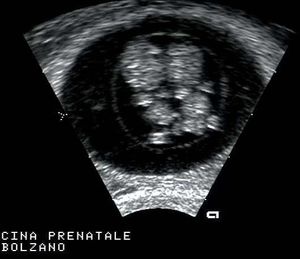

In a transvaginal coronal plane, you can see on the left-hand side of the fundus a flourishing pregnancy with an embryo of 9 weeks. In the last pictures of the clip a thin hypoechogenic endomiometrial layer is more easily seen.